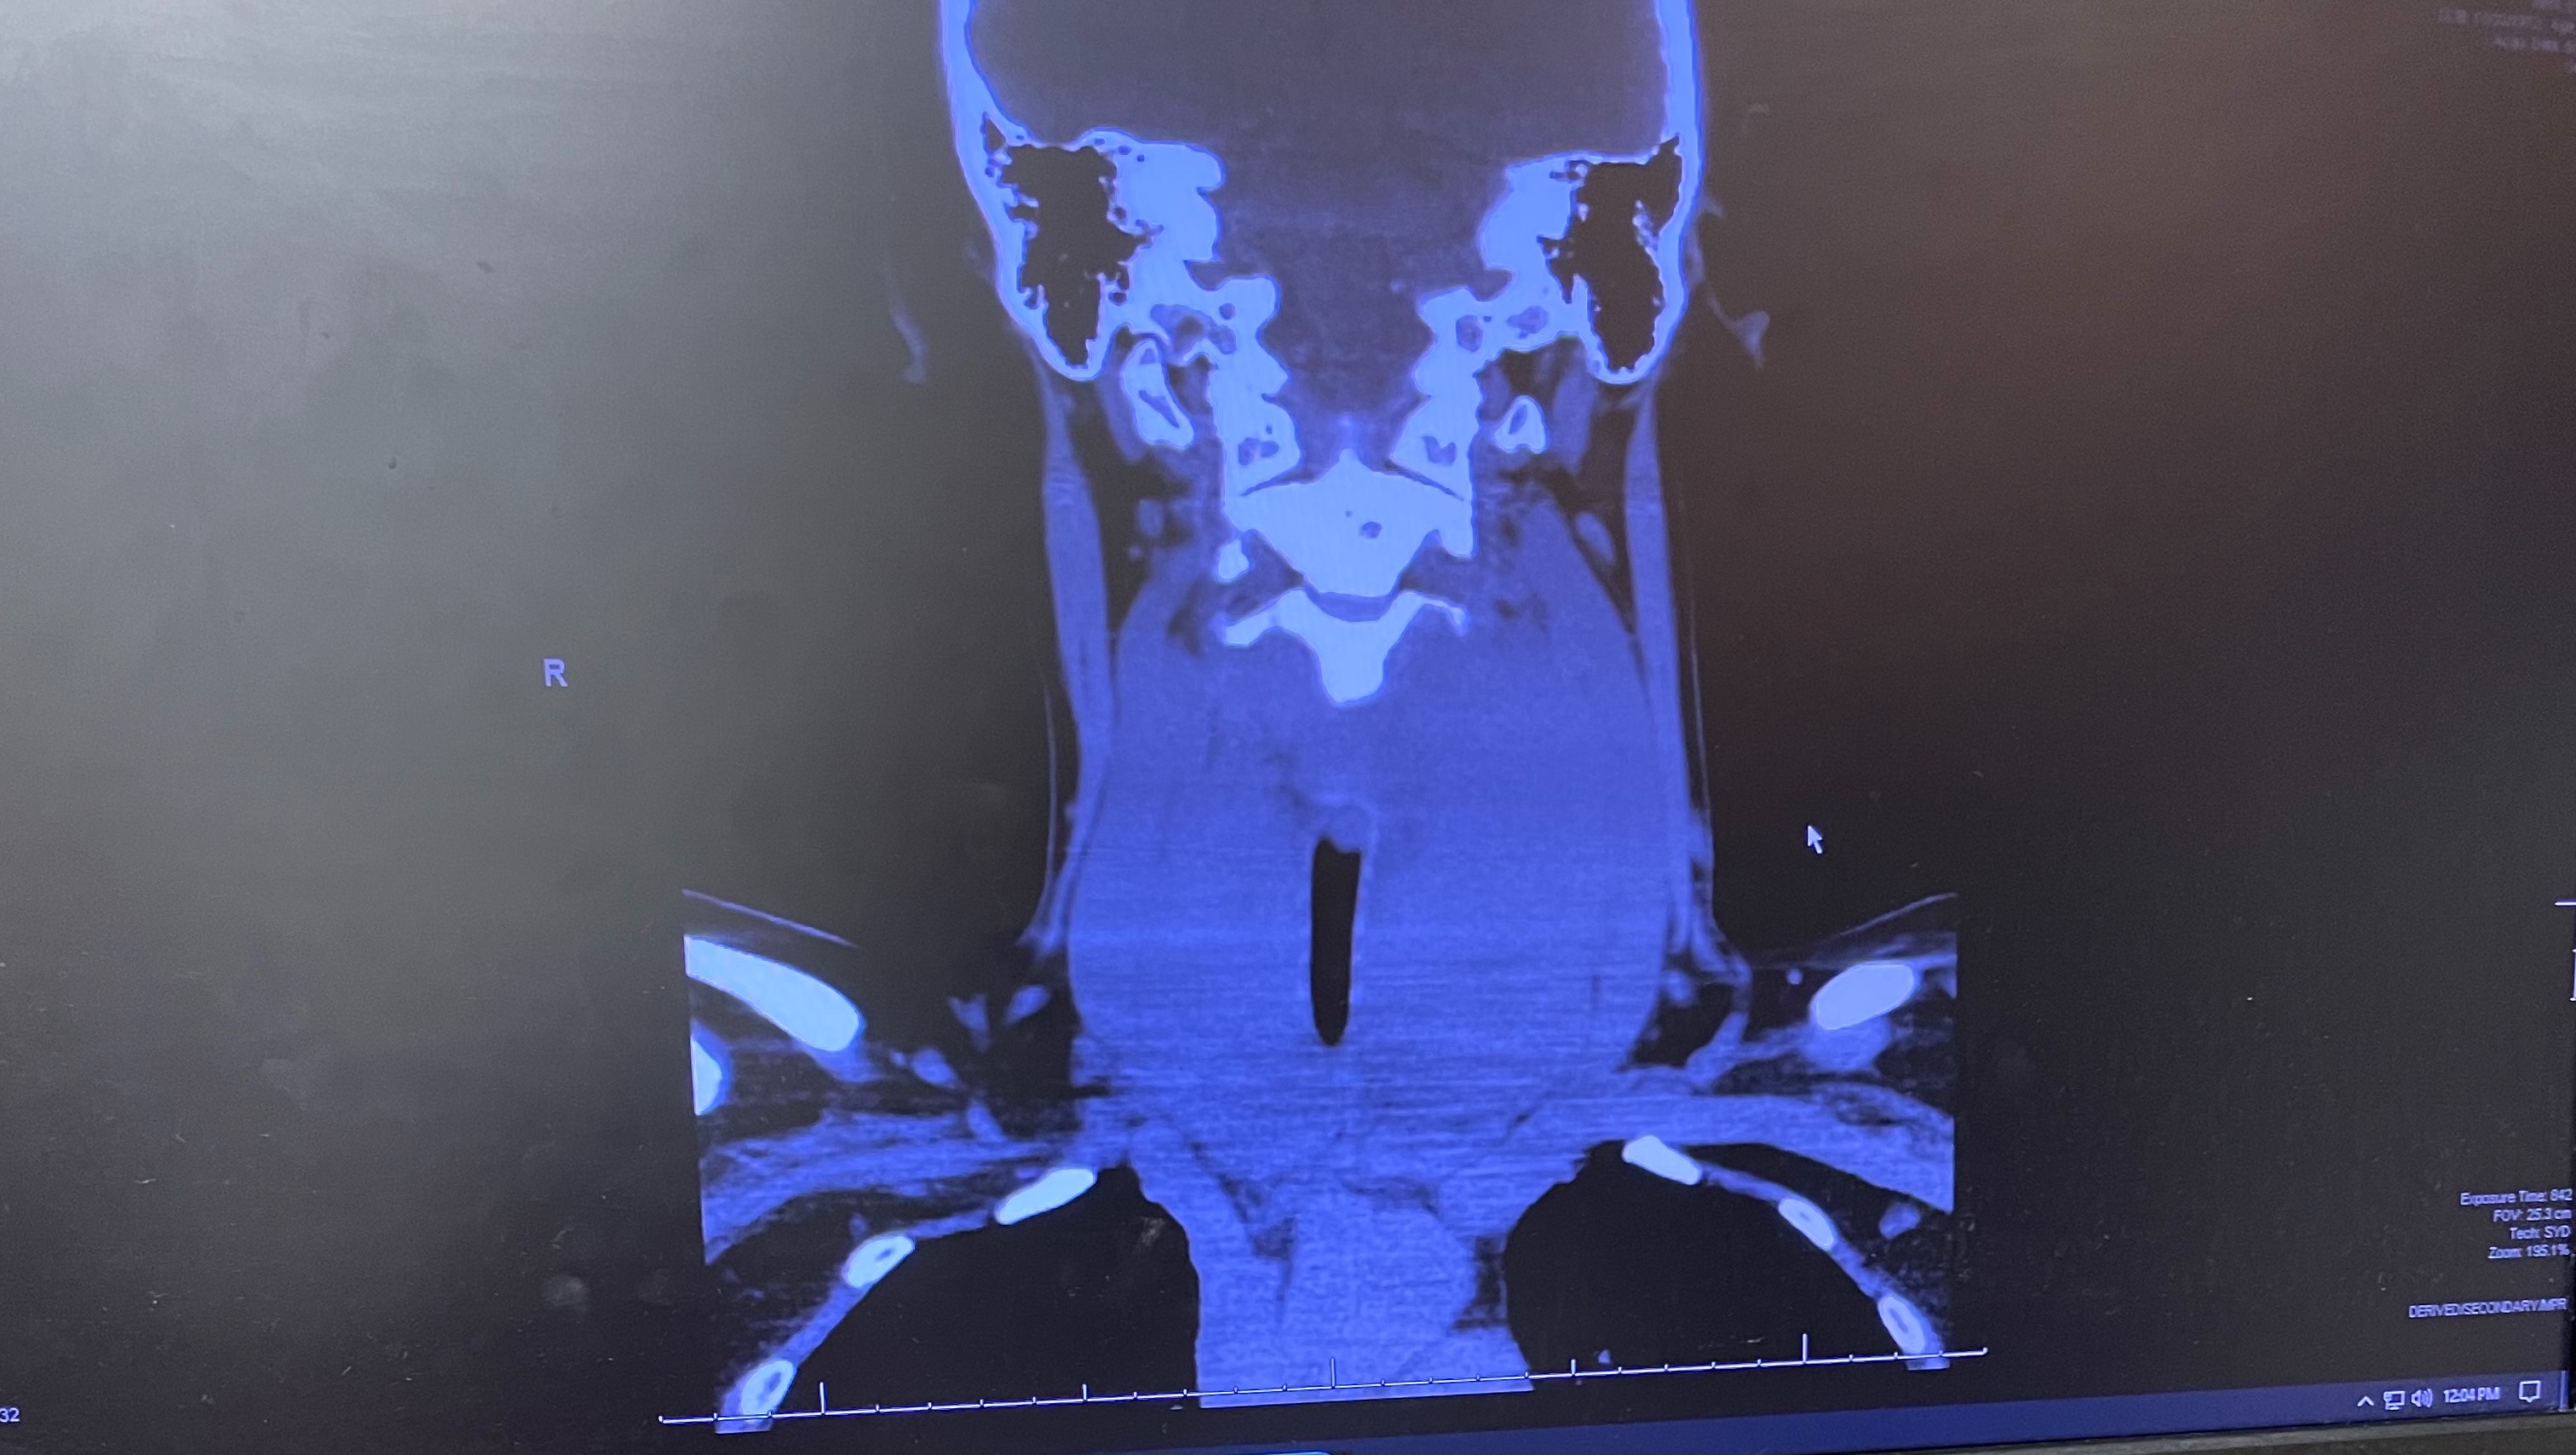

Katina is a kind and loving person, that has given much to many over the years. She has worked hard to climb the corporate ladder and was very successful. Then COVID-19 happened. When the world was forced to shut down, she and her family were placed in a situation where they had to live off of their savings for a long while. Just when things started to reopen, Katina had a stiff neck an inability to swallow. After a while she felt a lump in her throat. She went to a series of doctor appointments to find that she would be diagnosed with Stage 3 Primary Thyroid Lymphoma. She would soon learn that her cancer was extremely rare (less than 2% of all Lymphomas) and aggressive and she would have to fight for her life to beat the Lymphoma. Katina had surgery on June 23, 2021 . The doctors were able to remove a large 3.75 pound mass from her throat. Unfortunately they were not able to remove all of the cancer and a considerable portion of the mass has wrapped around her vocal chords causing her voice to be so faint, that her once strong voice is barely a whisper. The force she has to use to be make her voice heard is exhausting and painful. It causes her to be out of breath and gasp for air as she speaks. Her next surgery was on July 17th to place a port in her body for her upcoming Chemotherapy. Katina’s chemotherapy treatments are so aggressive that one of them is actually called The Red Devil. She receives a combination of Chemotherapy called the RCHOP. She had her first treatment on July 25th. While the doctors prepared her for how her body would respond, none of us expected the chemotherapy to make her as ill as it did. Katina has fought to be strong but unfortunately, these treatments have taken a toll. She lost her hair almost immediately, she is sick to her stomach, her skin hurts to touch, her whole body aches. At times she is delirious and in so much pain she wishes to sleep and not wake up. Katina has had to spend many days and nights in the hospital to get her levels up so that she, simply doesn’t die from her body reacting to chemotherapy. She has to receive treatments every 21 days until November, 2021. At this point, the doctors will be doing a PET scan to determine how her body has responded to the chemotherapy.

I have attached photos of Katina before cancer and after. I also attached photos of the mass removed and the scan of the mass while still in her throat. There is a short video Katina made when she still had strength for her non profit she hopes to someday get off the ground. If you have any questions please don’t hesitate to ask.